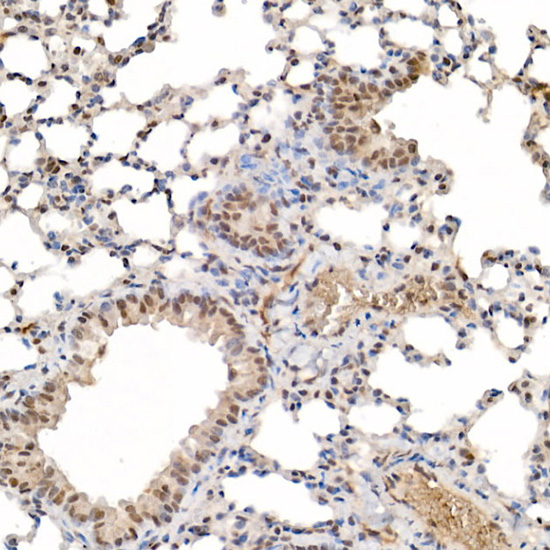

Immunohistochemistry of paraffin-embedded mouse lung using [KO Validated] HIF1?? Rabbit pAb.